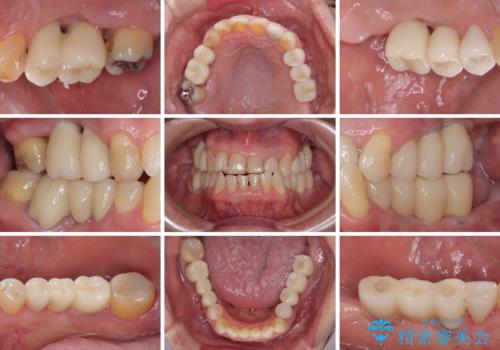

欠損の多い奥歯 インプラントによる補綴治療

上顎は左右ともに骨が少ない状態であり、特殊なドリルを用いた歯槽骨の拡大や自家骨挙上などを行いながらインプラントを埋入していくこととしました。

右下の銀歯も気になるとのことで、インプラント治療と並行してオールセラミックによるブリッジ補綴治療も行うこととしました。

地元に戻られる前に無事に治療を終えることができました。

今後は東京出張のタイミングでメインテナンスに通院していただきながら、インプラントの状態をチェックしていくことになります。